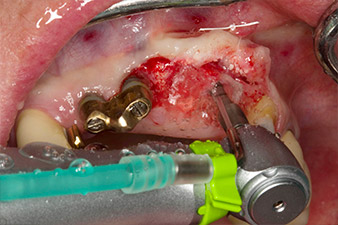

Following primary healing, the soft tissues were shaped using the basally lined bridge. Two months later the site was exposed by a slightly palatal alveolar ridge incision (Fig 2). The dimensions of the alveolar bone proved to be sufficient at position 22. Figures 2 and 4 show the preparation of the implant bed, the tapping and the implantation using Implantmed.

The new implantology motor was used with the appropriate W&H surgical contra-angle handpieces.